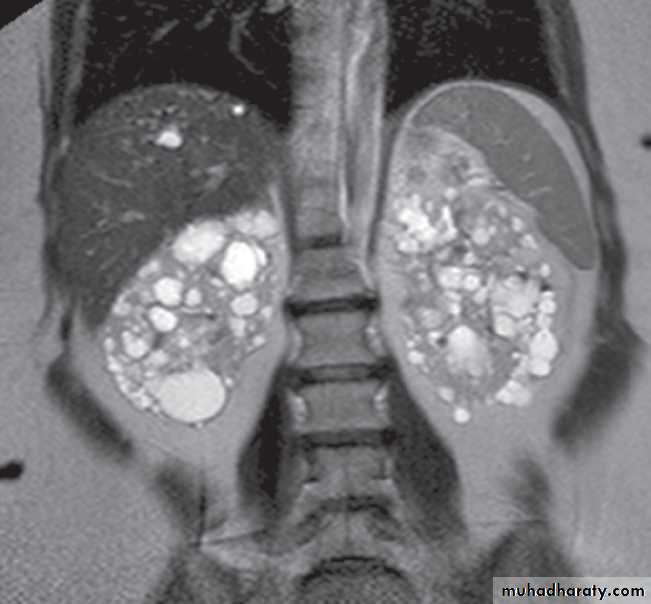

There are many varieties of cystic renal disease varying from simple cysts, which may be single or multiple, to complex renal dysplasias. The most frequent complex dysplasia encountered in clinical practice is autosomal dominant polycystic kidney disease.Renal agenesis